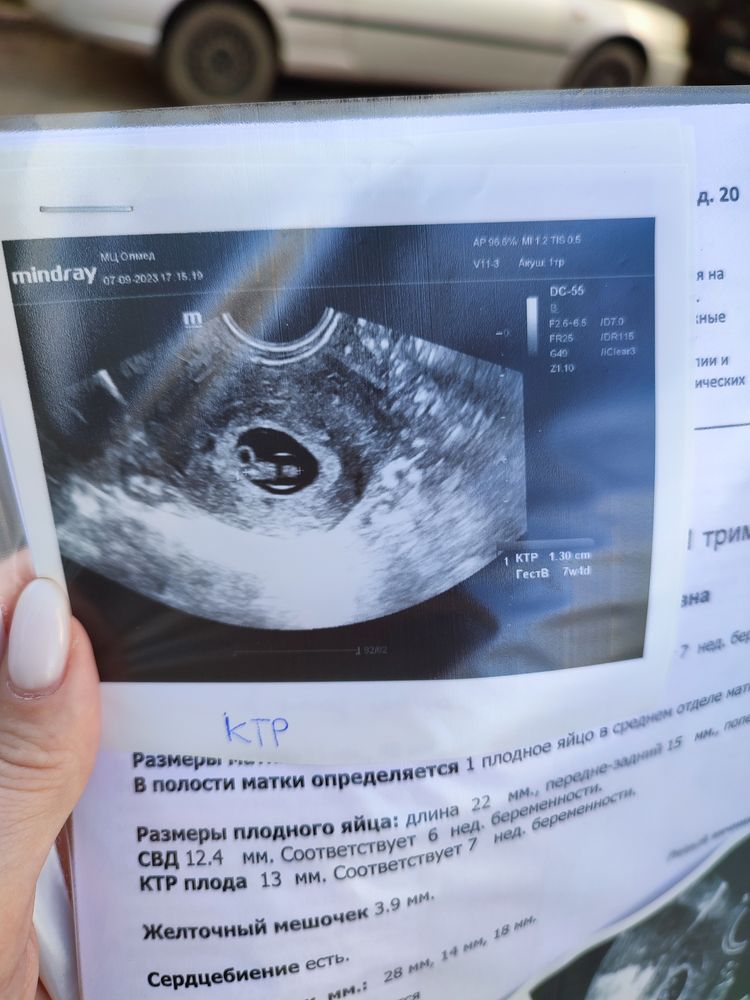

Девочки, добрый вечер всем! Была сегодня на 3 УЗИ, чтобы убедиться, что все хорошо ♥️ ктр вырос с 5, 9 мм до 13 мм (за 6 дней) , сердечко бьётся, всё хорошо, жм 3, 9 мм. Но меня напрягло СВД. 6 дней назад написали 14, 6 мм, а сегодня 12, 4 мм 😐 Как такое возможно, если эмбрион растёт 🫣 Погрешность? Почему в обратную сторону 🤷 Кто сталкивался с таким ?

Что-то неправильно вам написали свд. Если ктр 13, СВД как 12 мм то может быть...и вот смотрите, размер ПЯ 22х15, среднее как 12 мм получилось- непонятно. Короче, я считаю напечатали неправильную цифру, мож с предыдущего файла не исправили

Наташа Ростова, это средний внутренний диаметр плодного яйца, вроде как делают несколько замеров и среднее пишут)

У меня была похожая ситуация. ПЯ было 24мм в одной больнице, а через 5 дней прием в другой больнице и ПЯ намерили 23мм. Переживала абсолютно зря) Разные аппараты УЗИ и разные специалисты дали такую погрешность. Не переживайте, остальное же все растет и соответствует сроку ? Все будет хорошо, потом на следующем приеме размер догонит 🤗